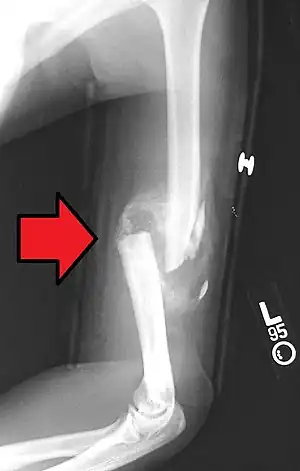

A transverse fracture of the humerus shaft -

A spiral fracture of the distal one-third of the humerus shaft -

A displaced supracondylar fracture in a child